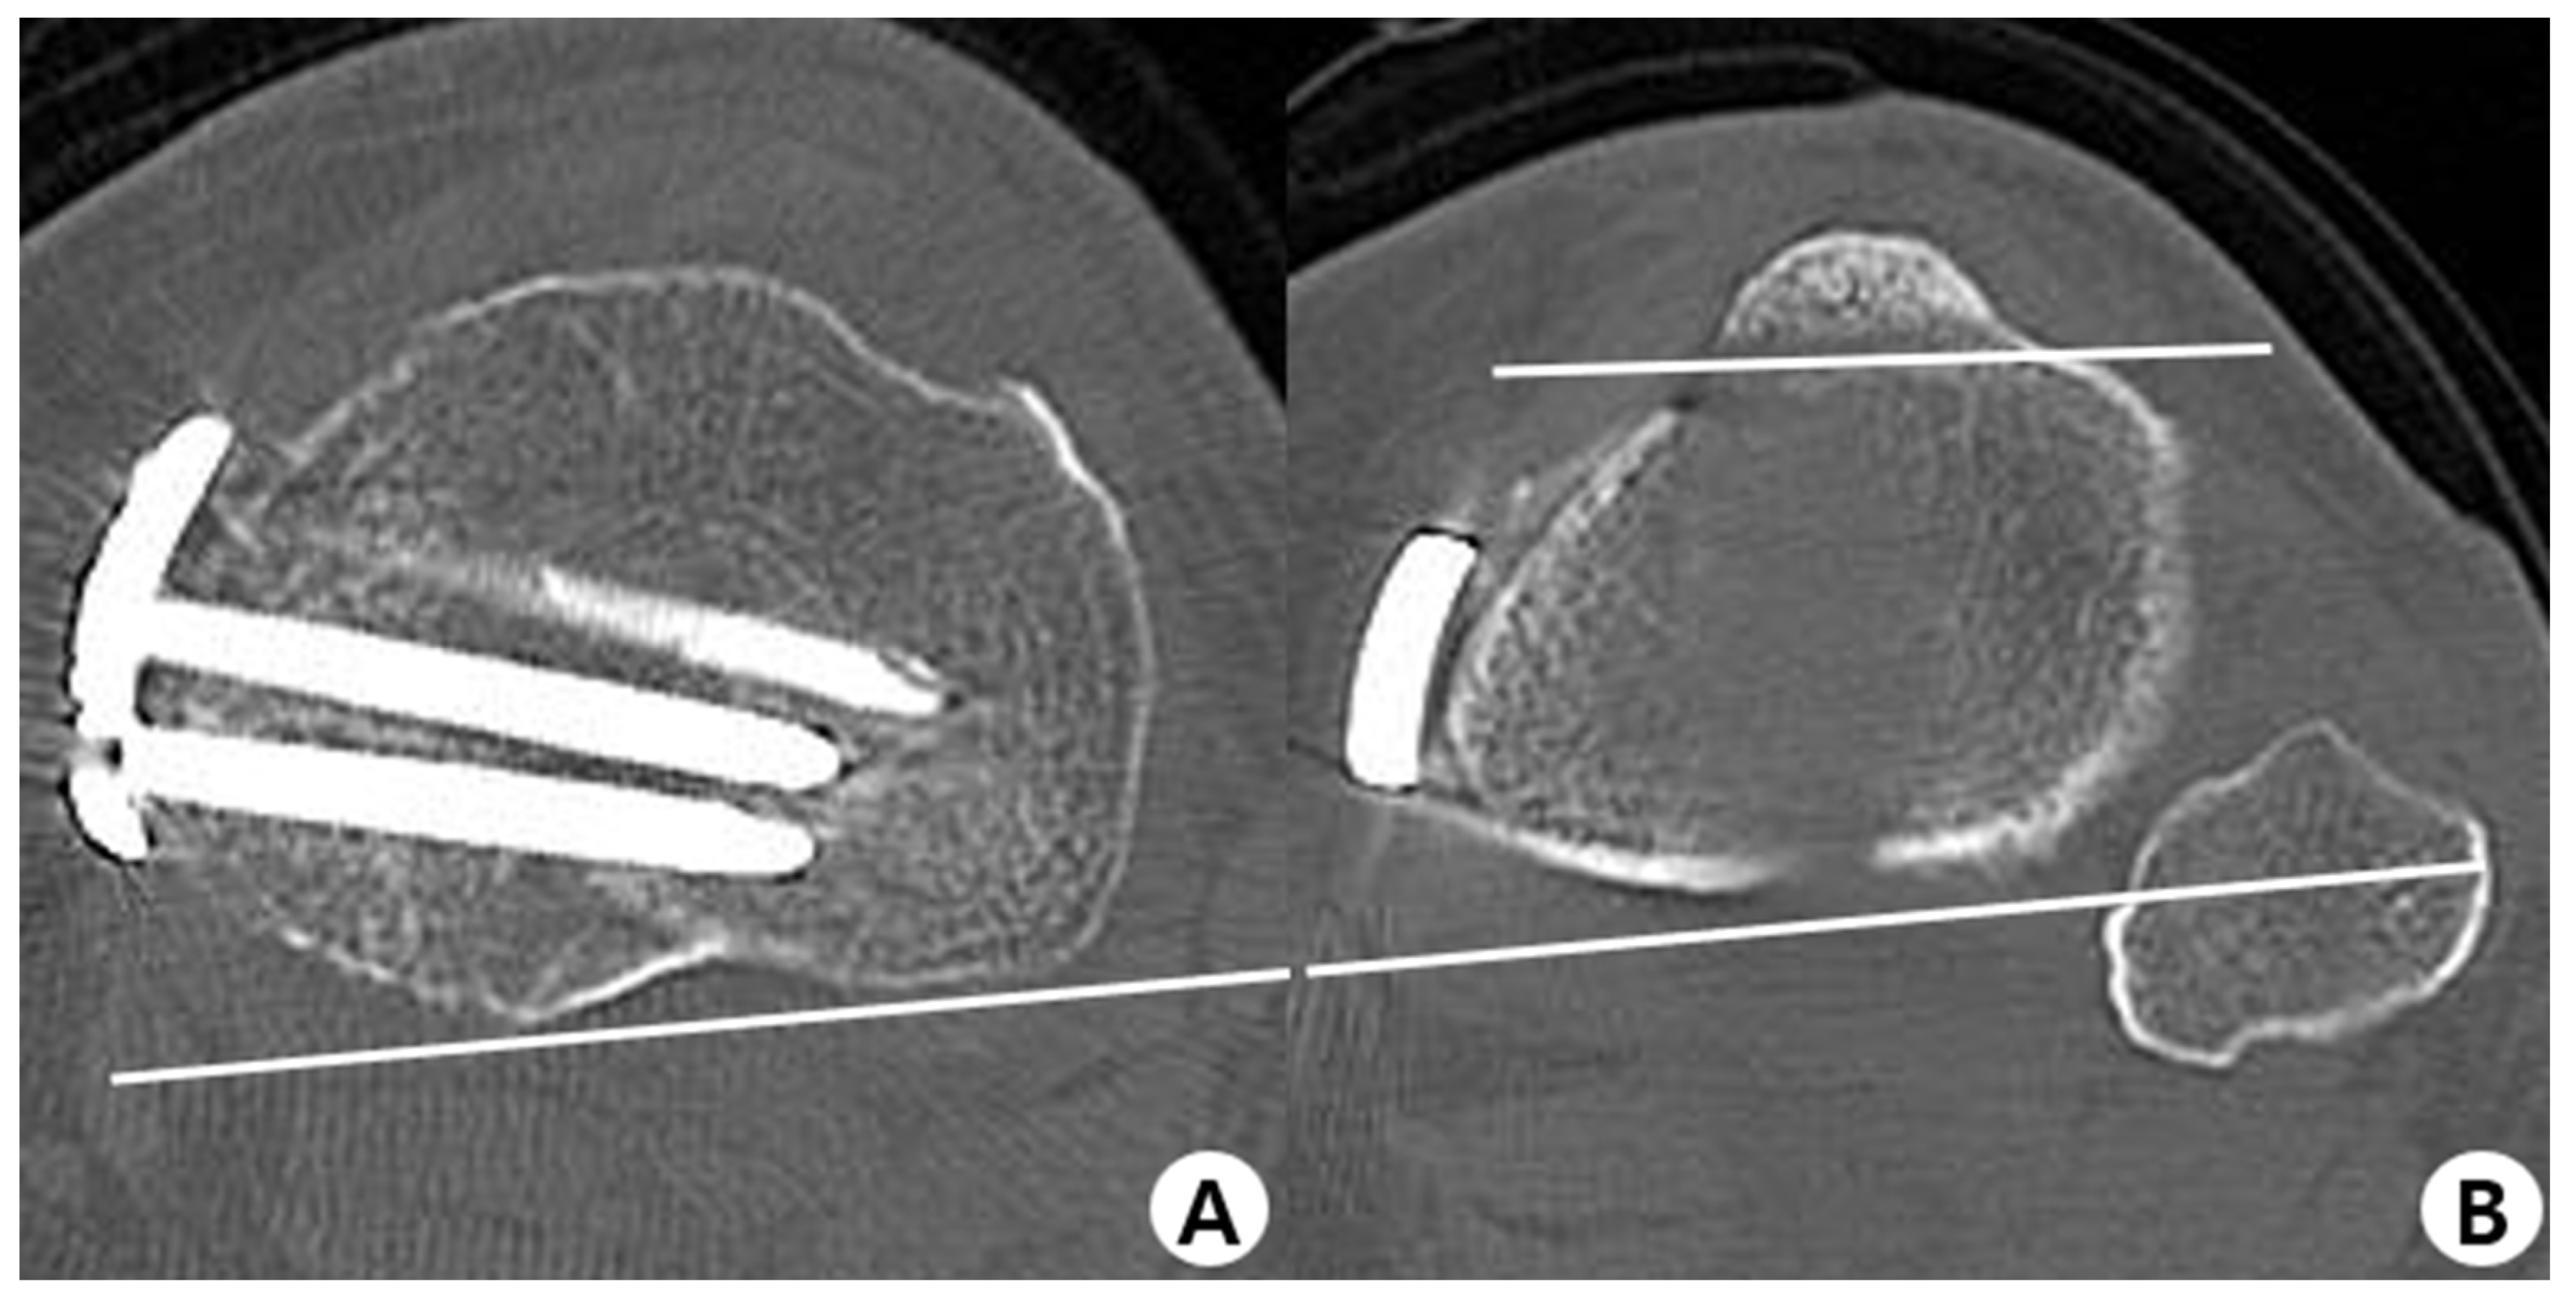

2.2. Evaluation Methods

2.3. Measurement of Parameters and Clinical Outcomes

2.4. Surgical Technique